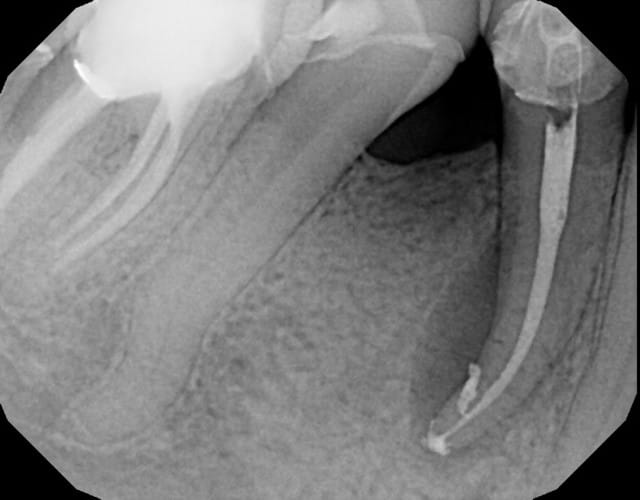

Mon endo de la semaine (je fais rarement plus d'une endo par semaine !)Joli canal lattéral.

Pour la 45, j'y touche pas si un jour besoin, pas mon truc les double courbes.